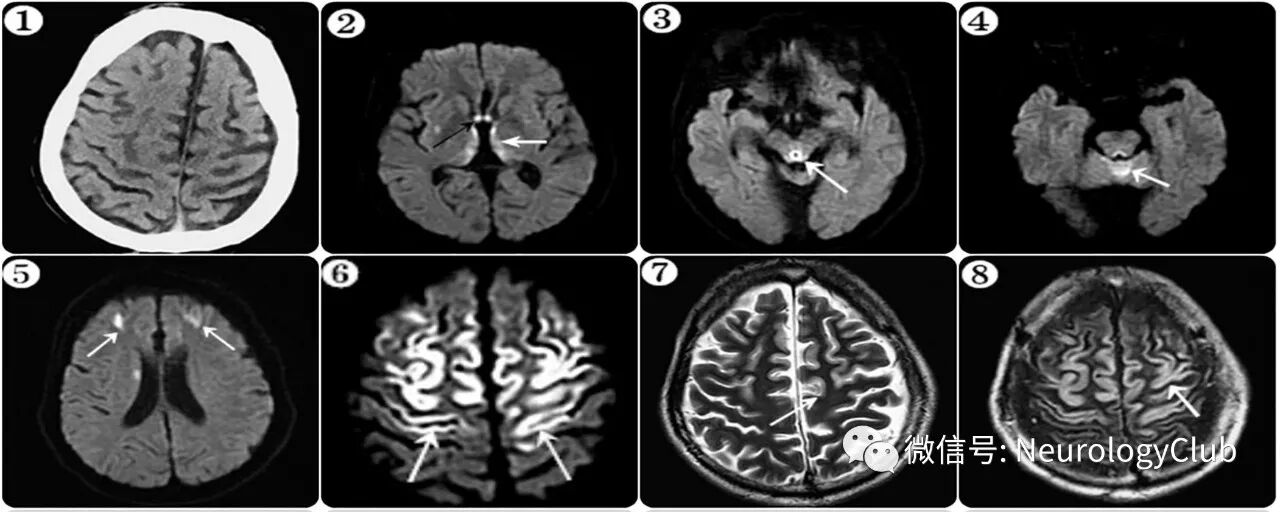

45岁男性,因2次全面性强直-阵挛发作和意识不清3小时被送至急诊。既往25年每天饮用6-9瓶啤酒,起病前未戒酒。有慢性酒精肝病史,未行系统治疗。入院查体:生命体征平稳,意识不清,Glasgow昏迷量表评分3分,双侧瞳孔等大等圆,直径3.0mm,对光反射迟钝,腱反射消失,右侧巴氏征阳性。余感觉、肌力、共济、步态等无法配合。起病后12小时的头颅MRI可见双侧额顶叶、内侧丘脑、三脑室旁、小脑蚓部以及导水管周围区域对称性T2WI/FLAIR高信号病灶,DWI上弥散受限(图)。脑电图提示中度异常。实验室检查:天门冬氨酸氨基转移酶218U/L(参考值:15-46),腰穿压力85mmH2O,脑脊液蛋白927mg/l,糖、氯化物和细胞数正常。

(图:①:CT未见明显异常;②-⑥:DWI;⑦:T2WI;⑧:FLAIR;MRI可见双侧额顶叶、内侧丘脑、三脑室旁、小脑蚓部以及导水管周围区域对称性弥散受限病灶

Wernicke脑病(WE)是一种严重的中枢神经系统代谢性疾病,因各种原因所致的硫胺素(维生素B1)缺乏所致。典型三联征为眼球运动障碍,共济失调和意识改变。典型影像学可见双侧乳头体,内侧丘脑,导水管周围灰质对称性异常信号。皮层受累少见。先前研究发现伴皮层病变的WE常见于非酗酒人群。而本例患者为慢性酒精成瘾,如此弥漫的额顶叶皮层异常信号,比较罕见。此外,基底节、小脑蚓部以及胼胝体也可受累。需要注意的是,影像学正常不能完全排除WE。癫痫发作为WE的少见临床表现,但可见于30%伴皮层病变的WE患者。其具体发病机制尚不清楚。对于临床确诊或高度怀疑WE的患者,应尽早补充硫胺素,防止症状进一步恶化,改善预后。